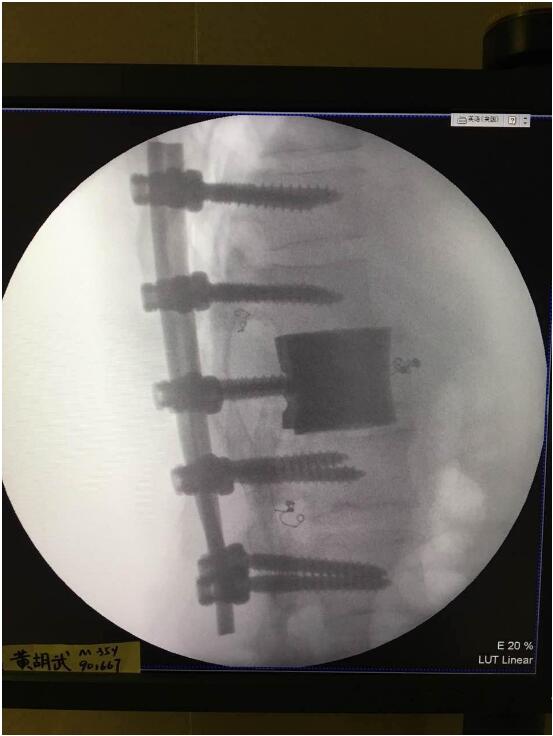

2018年2月7日華鈦三維與南方醫(yī)院脊柱骨外科聯(lián)合澳大利亞技術(shù)科學(xué)與工程院吳鑫華院士領(lǐng)導(dǎo)的莫納什大學(xué)增材制造研究中心合作的世界第一例3D打印個性化“人工椎體/椎間盤一體化“植入手術(shù)成功實(shí)施。不僅保住了病人的脊椎,還保住了其日后的活動能力。

這次手術(shù)是廣州華鈦三維骨科研究中心(華鈦三維骨科研究院)與南方醫(yī)院聯(lián)合澳大利亞技術(shù)科學(xué)與工程院吳鑫華院士領(lǐng)導(dǎo)的莫納什大學(xué)增材制造研究中心合作的世界第一例3D打印個性化人工椎體/腰間盤一體化植入手術(shù)。南方醫(yī)院脊椎及骨病外科鄭明輝副主任醫(yī)師在嶺南名醫(yī)陳建庭主任和朱青安教授指導(dǎo)下,與華鈦三維工程師陸國贊合作構(gòu)思設(shè)計(jì),澳大利亞莫納什大學(xué)增材制造研究中心主任吳鑫華院士團(tuán)隊(duì)進(jìn)行了一個多月的個性化鈦合金3D打印工藝研究,成功打印出符合病人要求的人工椎體/腰間盤一體化植入物。這次手術(shù)的成功,標(biāo)志著中國的3D打印植入物技術(shù)在骨科醫(yī)療領(lǐng)域達(dá)到世界先進(jìn)水平。

為了更好的完成手術(shù),陳建庭主任、鄭明輝副主任醫(yī)師等骨科專家與華鈦三維的3D打印專家從2017年10月份開始籌備該手術(shù)。考慮到每一個病人的脊椎形狀都存在差異,骨科專家認(rèn)為用一個現(xiàn)成的標(biāo)準(zhǔn)植入物不大可能匹配病人的生理參數(shù)。醫(yī)學(xué)專家和3D打印專家根據(jù)病人脊柱的CT掃描數(shù)據(jù),為病人的脊柱建立了精準(zhǔn)的3D圖像。根據(jù)這個圖像,治療團(tuán)隊(duì)就能夠設(shè)計(jì)并定制出屬于病人的個性化植入物。為了使個性化定制的人工椎體與病人椎體之間更好的融合,手術(shù)實(shí)施前治療團(tuán)隊(duì)先后設(shè)計(jì)了100多個方案,制作了數(shù)十個植入物的術(shù)前模型進(jìn)行研討。事實(shí)證明,手術(shù)最終使用的植入物是最適合手術(shù)和病人身體情況的。

利用3D打印技術(shù)生產(chǎn)出來的人工椎體是完全按照患者的解剖結(jié)構(gòu)完成脊椎結(jié)構(gòu)重建及固定的, 裝上一枚精準(zhǔn)的、個性化的人工脊椎,患者康復(fù)后完全可以正常地生活和工作。過去這種手術(shù)常常是使用鈦網(wǎng)內(nèi)填入自體或異體碎骨作為椎體間支撐材料,但鈦網(wǎng)一旦移位壓迫脊髓,患者就會有癱瘓的風(fēng)險(xiǎn)。這次手術(shù)中的脊椎植入物內(nèi)部具有經(jīng)過力學(xué)優(yōu)化設(shè)計(jì)的晶格結(jié)構(gòu),比傳統(tǒng)鈦網(wǎng)具有更強(qiáng)的承重力,金屬3D打印可以直接制造出這樣的復(fù)雜結(jié)構(gòu)。

最終在經(jīng)歷近八個小時后,病人的家屬終于等到了好消息:人工椎體/椎間盤一體化金屬植入物成功植入,手術(shù)順利。由于病人術(shù)中出血量小,生命體征平穩(wěn),他不用進(jìn)入ICU觀察,直接回到了普通病房?!艾F(xiàn)在我們都很高興,成功做出了世界首例人工椎體/椎間盤一體化金屬植入物,病人今后可以與常人一樣工作和生活?!编嵜鬏x醫(yī)生說。